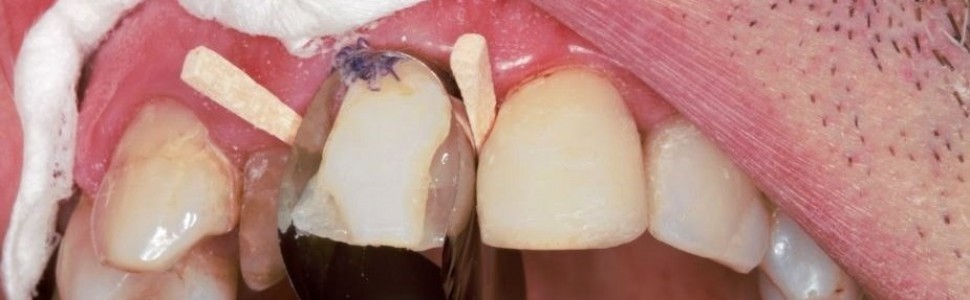

Poprawa estetyki uzębienia jest obecnie jednym z głównych zadań, przed jakimi na co dzień stają lekarze stomatolodzy. W sytuacji braku możliwości podjęcia przez pacjenta interdyscyplinarnego, długotrwałego leczenia alternatywą staje się postępowanie minimalnie inwazyjne. Do takich rozwiązań należy wykorzystanie materiałów złożonych. W pracy przedstawiono bezpośrednią kompozytową odbudowę zębów przednich.

Improving the aesthetics of the teeth is currently one of the main problems that dentists face on a daily practice. If the patient cannot take interdisciplinary, long‑term treatment, minimally invasive procedures become an alternative. Such solutions include the use of composite materials. The paper presents a direct composite restoration of the anterior teeth.